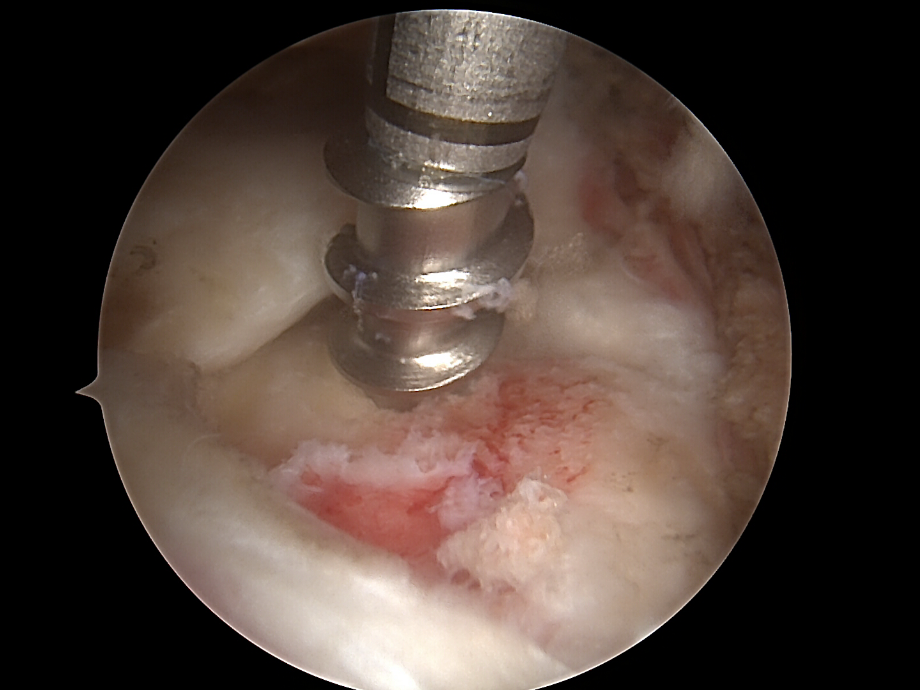

• Glättung und Anfrischen des Footprints (Sehnenansatzstelle) zur Förderung der Knochen-Sehnen-Heilung.

rotatorenmanschette von dr. timmel von ortho-timmel.at

Naht und Refixation

• Verwendung von Fadenankern (Suture Anchors), die im Humeruskopf eingebracht werden. Die Sehne wird mit Fäden durchstochen und zur Knochenoberfläche zurückgeführt.